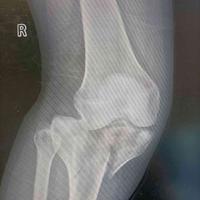

髌骨,空心钉,钛缆

查看图片需登陆

髌骨,空心钉,钛缆...

由 medjpg 发表于 2026-03-24 22:32